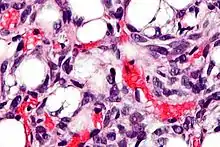

Micrografía que muestra un lipoblasto (parte inferior izquierda de la imagen) en un liposarcoma. Tinción de Hematoxilina-Eosina.

Los lipoblastos pueden verse en los liposarcomas[5] y característicamente tienen un citoplasma abundante, claro y multivacuolado y un núcleo mellado y con tinción oscura (hipercromático).